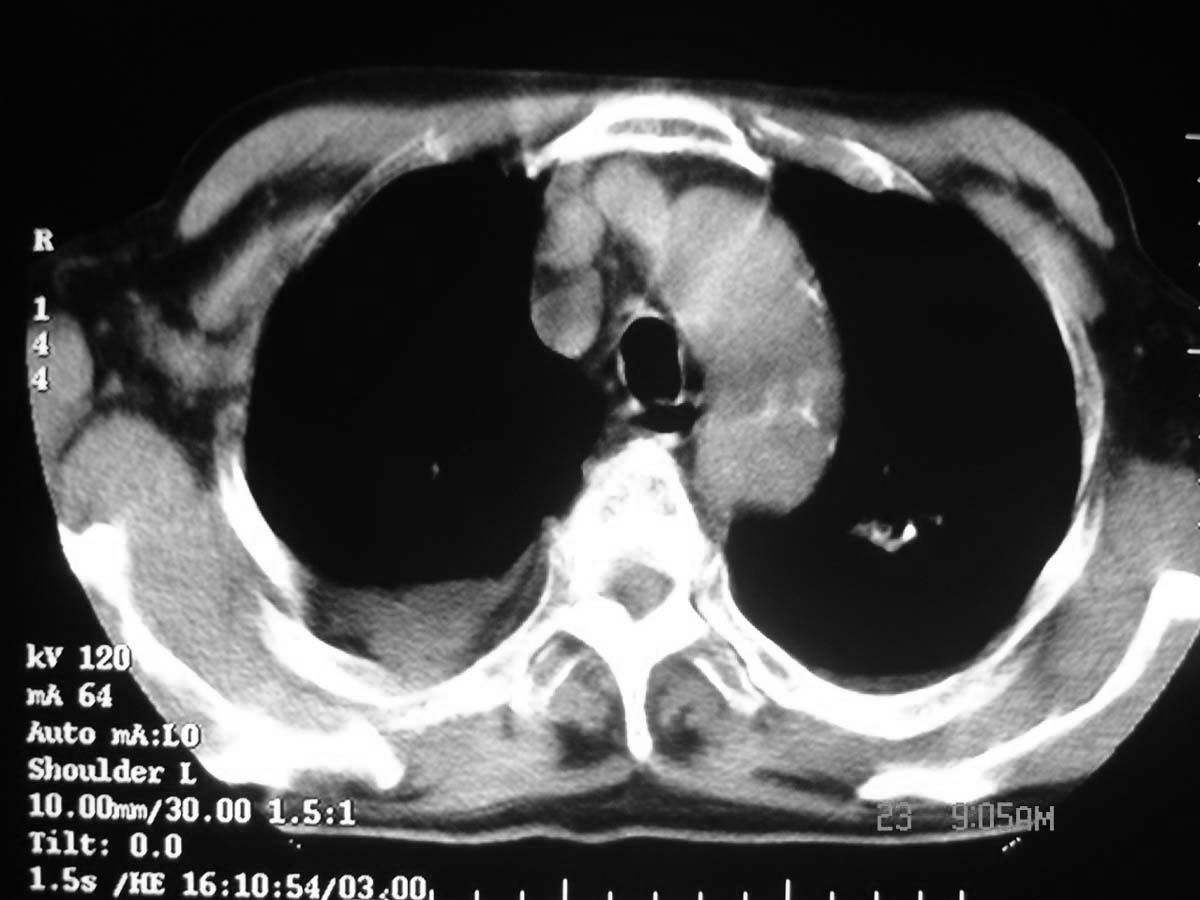

以下是引用守望可可西里在2006-11-23 14:33:00的发言:[br][br] 糖尿病病人很容易继发结核,病人又有双侧胸膜增厚、粘连、胸腔积液以及双上肺的斑片状、条索状影结核病灶影,以一元论考虑,右下肺病变首先考虑干酪性肺炎,可以正规抗炎治疗后复查,排除一般的肺炎。